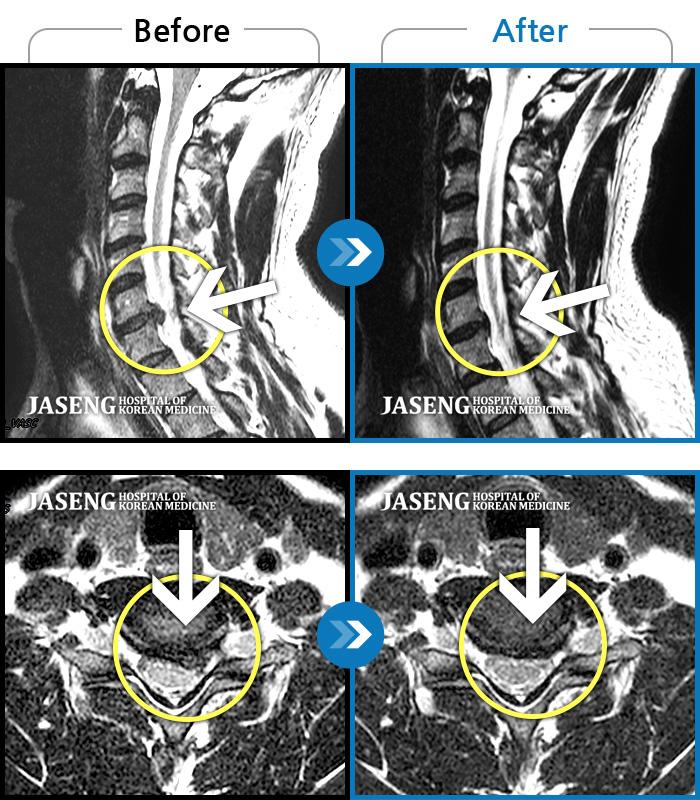

목디스크 근보치료를 위해 여러군데 병원과 경락지압을 거쳤으나 별 차도가 없었으나

자생병원 강만호원장님께 치료받고 지금은 증상이 거의 사라졌습니다.